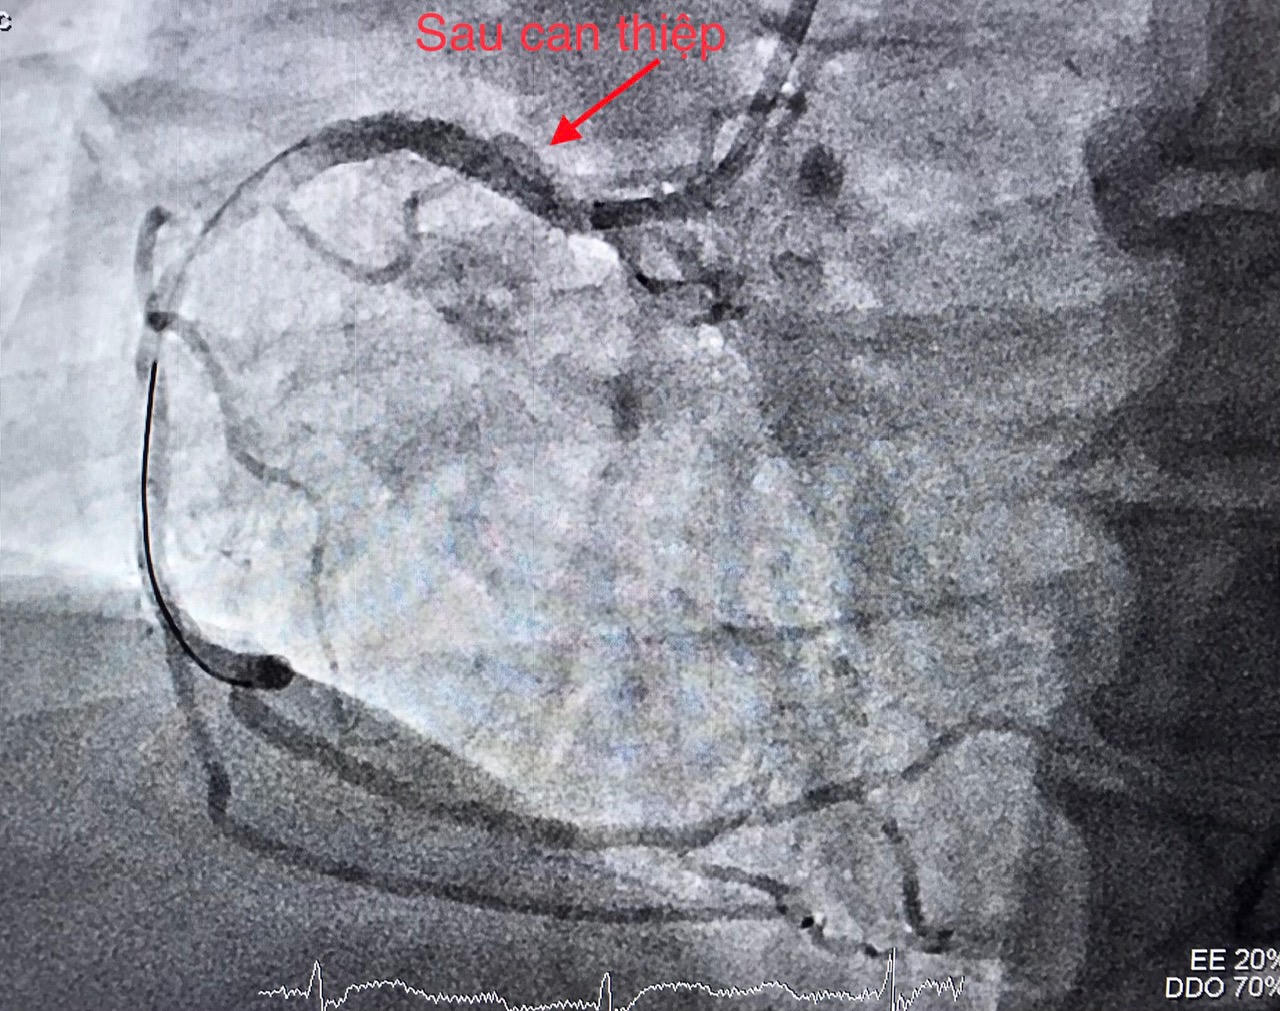

Các bác sĩ BVĐK TW Cần Thơ tiến hành hội chẩn với ê-kíp trực cấp cứu tim mạch can thiệp, sau đó chỉ định can thiệp mạch vành cấp cứu bệnh nhân.

Thời điểm chuẩn bị đặt ống thông để can thiệp mạch vành, bệnh nhân liệt nửa người bên trái và nói đớ. Nhận định đây là một trường hợp hiếm gặp phối hợp giữa nhồi máu cơ tim cấp (do tắc động mạch vành) và nhồi máu não cấp (do tắc một mạch máu ở não), ê-kíp can thiệp mạch máu não lập tức được báo động để cùng phối hợp điều trị cho bệnh nhân. Kết quả CTscan não đúng như chẩn đoán.

Ê-kíp can thiệp tim mạch trong thời gian khoảng 40 phút đã hoàn tất nong động mạch vành bị tắc và tiến hành đặt giá đỡ (stent), giúp tái lập dòng máu nuôi tim. Ngay sau đó ê-kíp can thiệp mạch não chụp kiểm tra phát hiện tắc động mạch não giữa bên phải; thủ thuật lấy huyết khối tái thông mạch máu bị tắc với thời gian 20 phút.